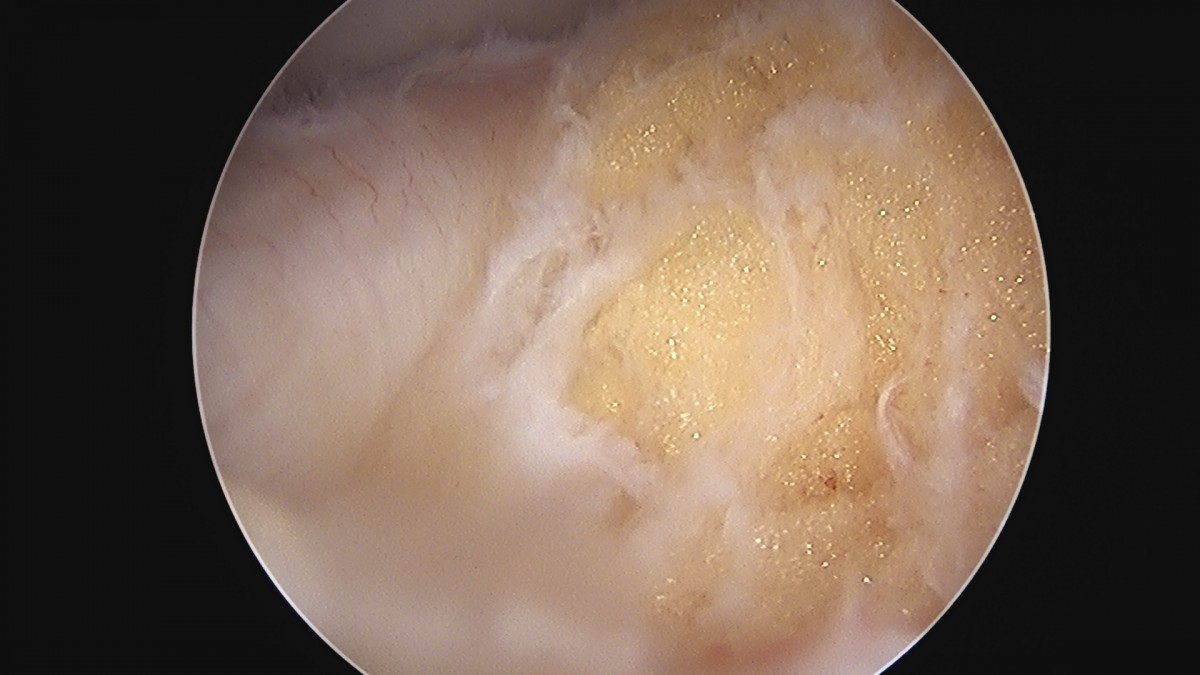

이재상원장님 무릎 반월상 연골판 절제술 김건O 환자

dae765e4d9ac96aee867c9d6292d8784_1758006494_0555.jpg